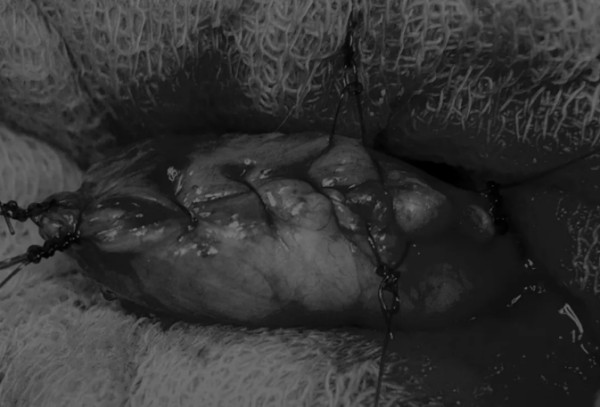

在中线开腹手术后,确定膀胱,将其取出并隔离(图1)。为了使膀胱持续暴露,可在膀胱中线两侧各放置一根固定缝线(图2)。

图2 在手术过程中,还需要另外两根固定缝线来保持膀胱切开术的膀胱边缘处于暴露状态